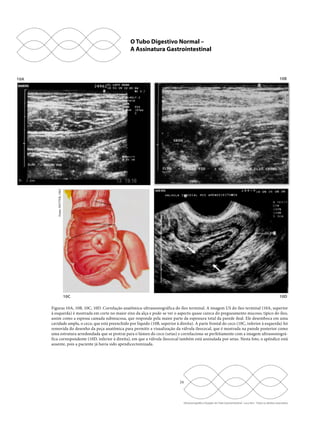

Figuras 10A, 10B, 10C, 10D. Correlação anatômica-ultrassonográfica do íleo terminal. A imagem US do íleo terminal (10A, superior

à esquerda) é mostrada em corte no maior eixo da alça e pode-se ver o aspecto quase careca do pregueamento mucoso, típico do íleo,

assim como a espessa camada submucosa, que responde pela maior parte da espessura total da parede ileal. Ele desemboca em uma

cavidade ampla, o ceco, que está preenchido por líquido (10B, superior à direita). A parte frontal do ceco (10C, inferior à esquerda) foi

removida do desenho da peça anatômica para permitir a visualização da válvula ileocecal, que é mostrada na parede posterior como

uma estrutura arredondada que se protrai para o lúmen do ceco (setas) e correlaciona-se perfeitamente com a imagem ultrassonográ-fica

correspondente (10D, inferior à direita), em que a válvula ileocecal também está assinalada por setas. Nesta foto, o apêndice está

ausente, pois a paciente já havia sido apendicectomizada.

Figuras 11A, 11B, 11C. US do cólon. A imagem anatômica do cólon é mostrada com suas haustrações características neste desenho

(11A, superior à esquerda), e o lúmen mais amplo do que nos demais segmentos intestinais. A imagem US pela via transvaginal (11B,

superior à direita) mostra as haustrações típicas dessa parte do tubo intestinal, mas apenas a superfície anterior é demonstrável, pois

a parede posterior está muito tênue devido à atenuação pelo conteúdo sólido-pastoso e gasoso do lúmen, fortemente ecogênico nesta

imagem. A imagem inferior (11C) é uma fotomontagem que uniu duas porções do colón sigmoide justapostas obtidas pela via trans-vaginal

para mostrar as haustrações da alça ao longo de um trajeto maior.